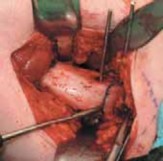

Wound Closure

3. The vastus lateralis is reattached to its origin on the trochanteric ridge with absorbable braided 0 suture so that the entire plate is covered (

TECH FIG 5

). Two or

three tacking sutures are used to reattach the posterior edge of the vastus fascia to the septum.

27. The wound is closed in layers, including the fascia lata, the subcutaneous tissue, and the skin. Absorbable running subcuticular suture will obviate the need for suture removal.

--- TECH FIG 5 • Repair of vastus lateralis to its origin to cover the blade plate. #### PROXIMAL FEMORAL DEROTATIONAL OSTEOTOMY WITH 90-DEGREE AO BLADE PLATE: PRONE TECHNIQUE18

3. The approach and dissection are identical to those de-

scribed for the supine technique; only the orientation must be remembered with the anterior vastus lateralis now falling away from the operative field (

TECH FIG 6A

).

28. The torsional profile in the prone position is much easier to verify and compare with the contralateral side (

TECH FIG 6B,C

TECHNIQUESTECH FIG 6•

Proximal femoral derotation osteotomy using the prone technique.

A.

Orientation of the exposure in the prone position.

B,C.

Intraoperative ability to estimate the torsional profile. PROXIMAL FEMORAL DEROTATIONAL OSTEOTOMY WITH A REGULAR LOW-CONTACT DYNAMIC COMPRESSION (LCDC) PLATE tational osteotomy can be stabilized with a regular LCDC plate but might be adequate in most children.